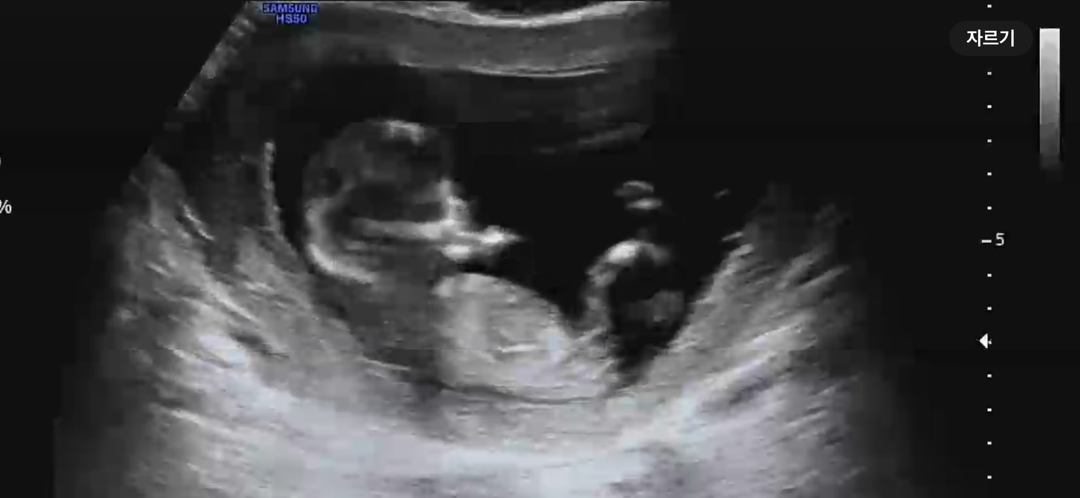

아들일까요? 딸일까요?

잘보시는분 계신가요?